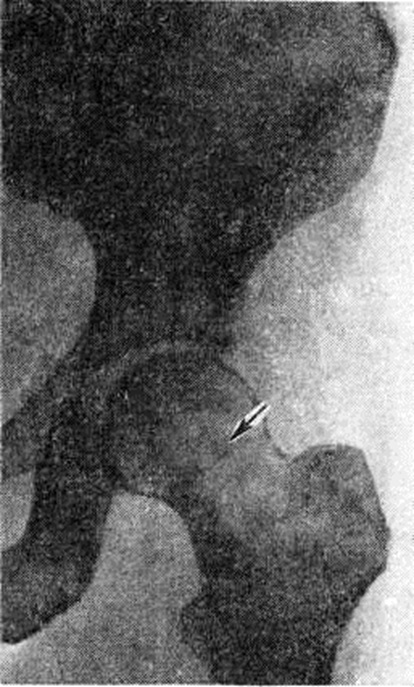

В распознавании хондросаркомы важная роль принадлежит рентгенологическое исследованию — данным рентгенографии (смотри полный свод знаний), томографии (смотри полный свод знаний) и ангиографии (смотри полный свод знаний). Важным рентгенологическое признаком хондросаркомы является нарастание имеющихся или возникновение новых патологический изменений при повторных рентгенологическое исследованиях. Преимущественно внутрикостная хондросаркома характеризуется деструкцией костной ткани, зона которой занимает большую часть или весь костномозговой канал поражённой кости (рисунок 1). Опухоль имеет нечёткие границы, что особенно заметно в области костномозгового канала. Структура участка поражения, как правило, неоднородная за счёт многочисленных включений солей кальция в виде крапа, островков или конгломератов.

Рис. 1.

Рентгенограмма тазобедренного сустава при хондросаркоме в области шейки бедренной кости с преимущественным внутрикостным типом поражения (прямая проекция): неоднородный участок деструкции костной ткани с нечёткими контурами (указан стрелкой).